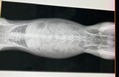

術前検査のレントゲン

特に問題ありません。

※クリックで拡大見れます。